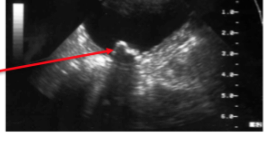

What is this?

US of cystolith note the acoustic shadows